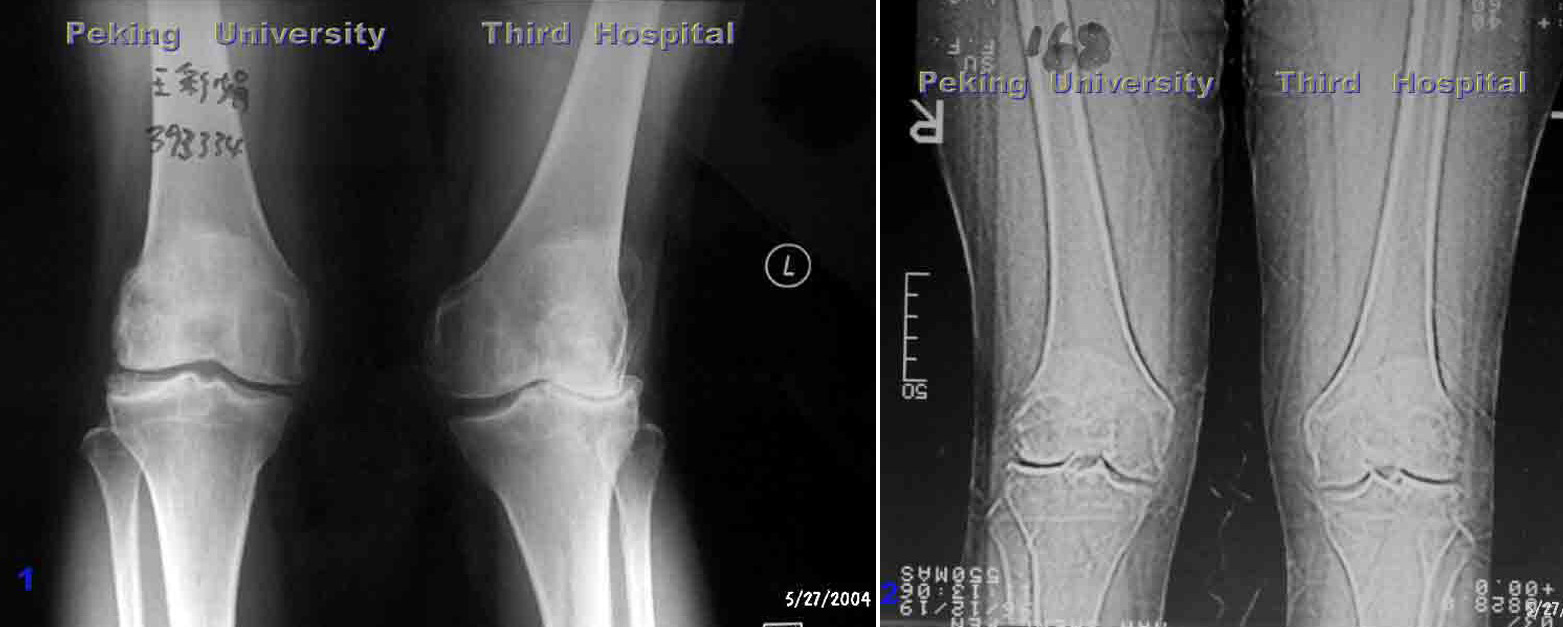

膝关节内侧间隙狭窄,适合单髁置换,手术后恢复快,

关节活动最大限度保留